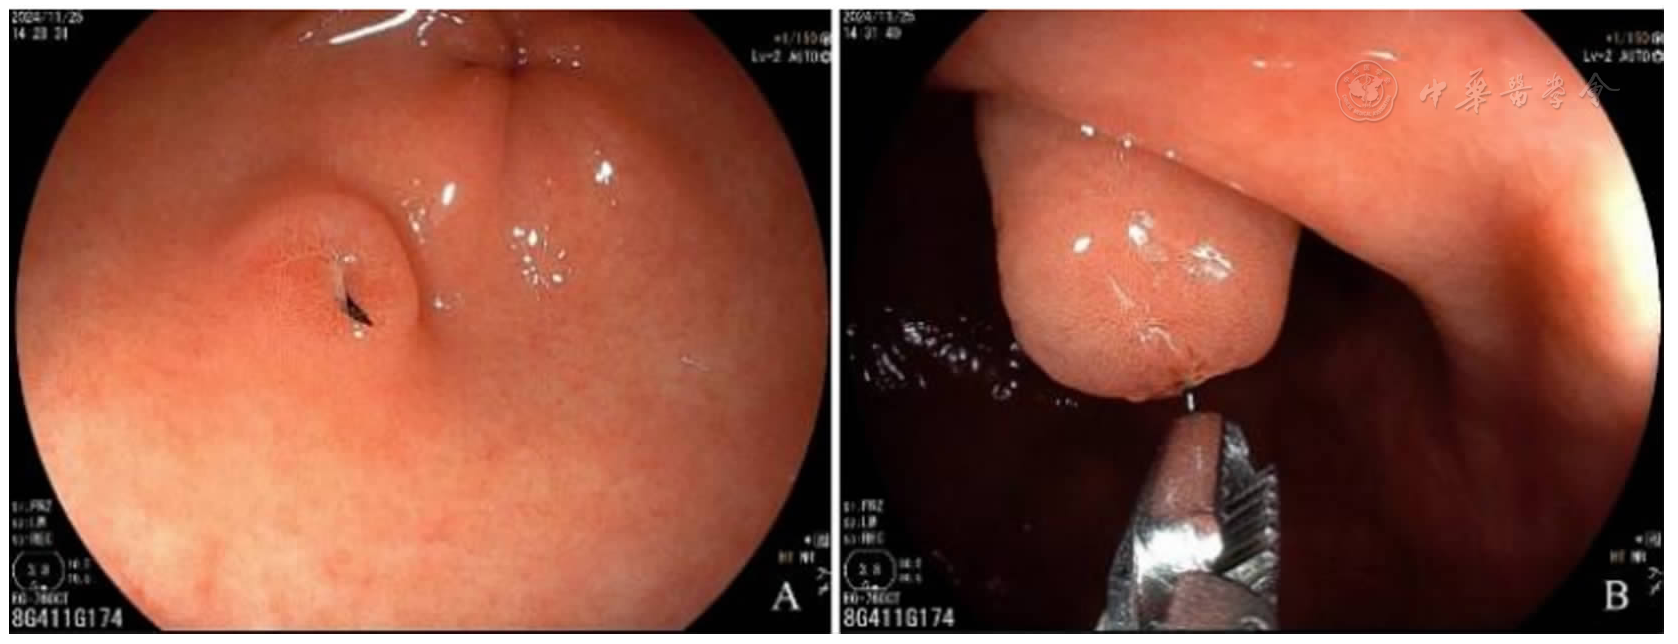

图2 胃镜检查注:A:胃窦大弯前壁近幽门可见金属针样异物;B:异物钳反复尝试不能取出